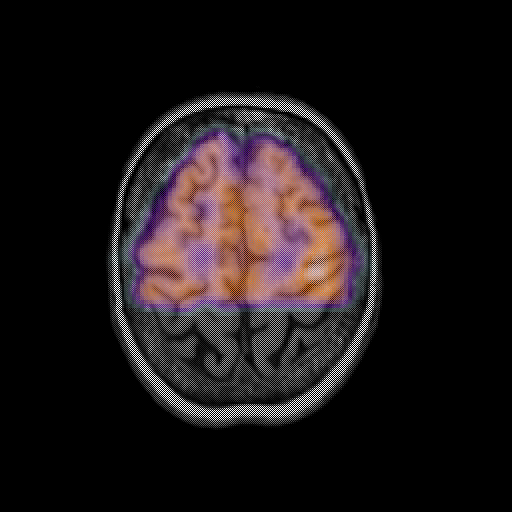

overlay: Slice 42

Slice 42

MRCBFCBF with

T1PDT2T1PDT2